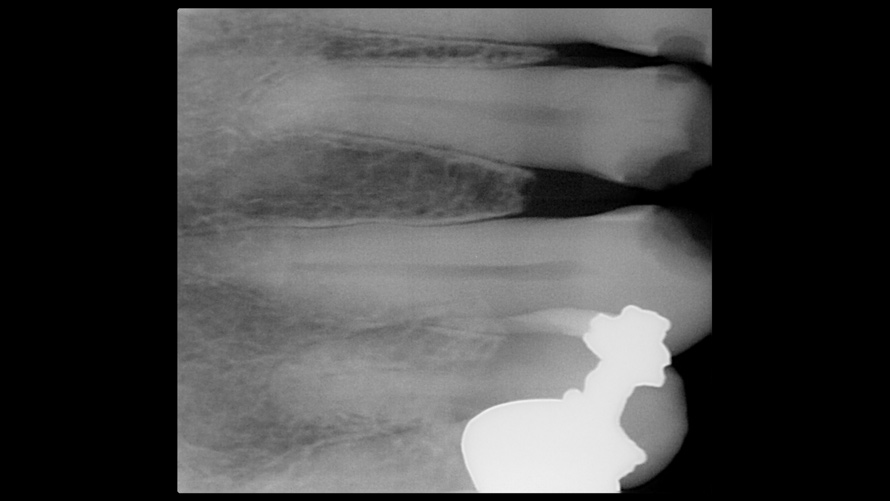

(14. and 15.) Photograph of fractured right lateral incisor taken with a smartphone and an EALS device during patient presentation for emergency treatment shown with accompanying radiograph.

Figure 14

Figure 15